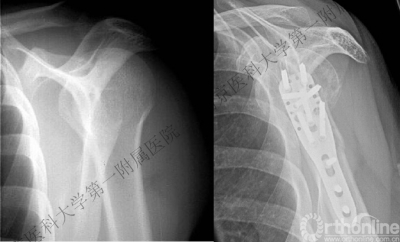

病例1

男性,40岁,摔伤后右肩关节肿痛、活动受限2天。

术后肩关节X线正位片

病例2

男性,48岁,坠落伤致左肩关节肿痛、活动受限1天。